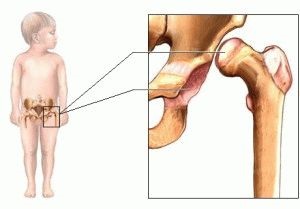

Dintre nou-născuți și sugari boli mai puțin frecvente - displazie de sold. Displazia - tulburări în dezvoltarea țesutului osos sau. Displazia de sold - o încălcare a elementelor în dezvoltarea pieselor osoase și a ligamentelor articulare: o îmbinare musculare capsulă, acetabul, capul femural.

capsula articulară atunci cand boala incepe sa se intinda, ligamentele nu sunt în măsură să dezvolte, acetabul ia forma unei elipse plat. Cele mai frecvente boli observate la copii și sugari, este considerată a fi o boală congenitală.

Sugarii de la naștere până la vârsta de 3-4 luni, structura standard anatomice ale oaselor si ligamentelor este foarte diferit de articulații pentru adulți. Acetabulum la copii dezvăluie o formă plată, formată în ființa umană într-o poziție înclinată. La sugari, acetabul este situat aproape vertical. Odată cu creșterea medicului copilului monitorizează unghiul acetabular, în dezvoltarea normală a diagnosticului este eliminat.

Acetabular displazie - o formă de patologie de dezvoltare anormală a acetabulului. Acesta evidențiază principalele tipuri:

- Predvyvih. Încălcarea dezvoltării și formarea mușchilor, ligamentelor și articulațiilor șoldului. Corpul de acetabulare detectează locație greșită, este teșite. Există o ușoară deplasare a femurului proximal de acetabul. Acest tip de displazie acetabulara identifica rapid medici în diferite moduri.

- Subluxație. Subluxatie de sold este definit ca o deplasare mai mare a capului în șold decât la predvyvihe. Capul vine sub buză cartilajului de îndoire înapoi în sus și-l alunecare în raport cu poziția normală. Din acest motiv, a ligamentelor intinse.

- dislocarea completă a șoldului. Capul merge complet departe de poziția dorită. În cazul în care capul normală este poziționat în cavitatea, cu boala capului femural este situat în afara acestuia. RIM cartilaginoase este îndoit în interior, în timp ce în starea fixată. Ligamentele devin întinse.